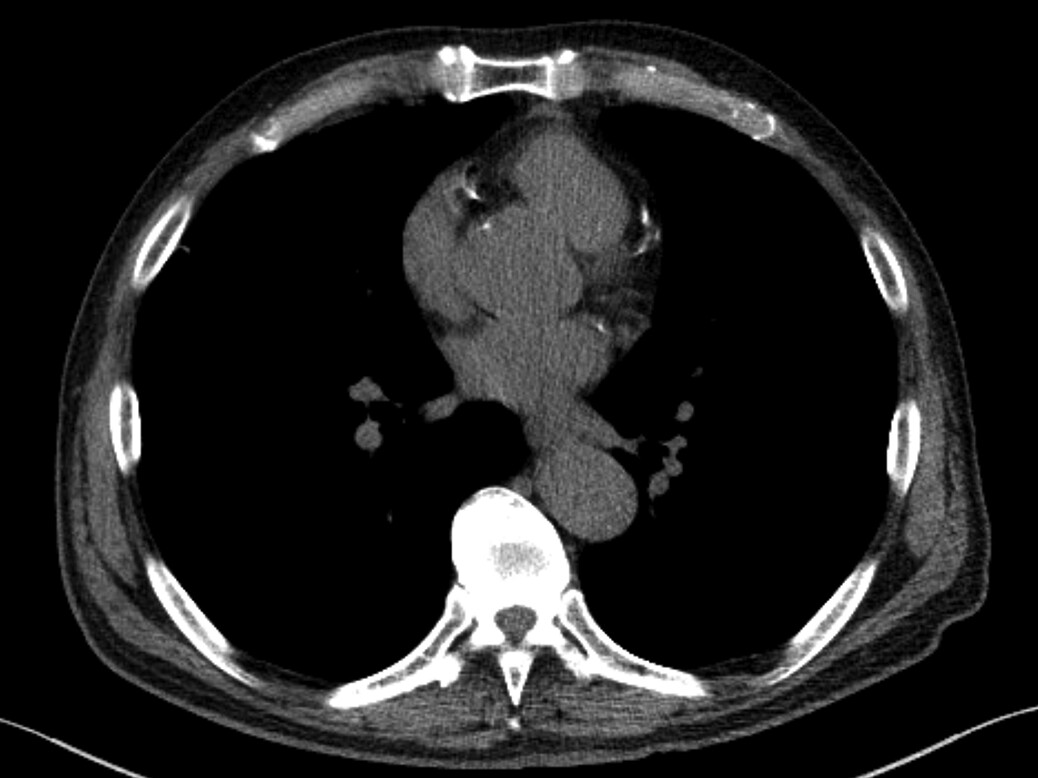

Fig. 2—73-year-old patient who underwent lung cancer screening by LDCT of the chest. Axial CT image shows coronary artery calcification (CAC). CAC was assessed as severe by consensus visual analysis.